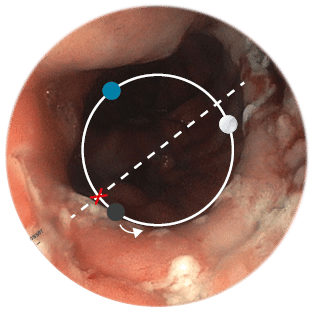

Positionsermittlung

Die korrekte Positionierung der BARS® Anchor ist entscheidend für eine erfolgreiche Behandlung.

- Mit einer gedachten Mittellinie die Anastomose in zwei Hälften teilen.

X = Austrittspunkt Endoskoparbeitskanal - Die Anchor knapp unterhalb der Mittellinie platzieren.

• = BARS® Anchor Black, • = BARS® Anchor Silver. - Der Kalibrierballon (•) definiert das Restlumen im gegenüberliegenden Halbkreis.

Beispiel 1*

Anvisieren der Applikationsstelle.